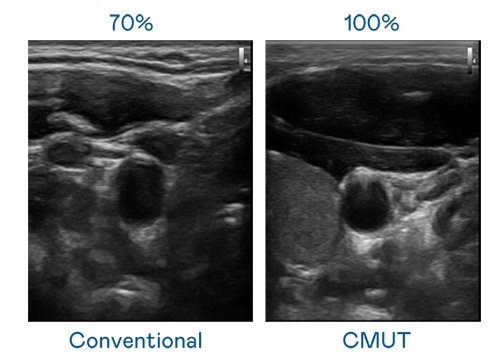

CMUT 技術是一種用電容式微機電元件來產生超音波訊號的技術。與傳統 PZT 壓電式技術相比,CMUT 頻寬增加 30%,更寬頻的超音波訊號讓影像解析度大幅提升,是實現高影像品質醫療超音波掃描、促進精準醫療發展的關鍵技術。

超音波影像的解析度高低,首先取決於探頭能發出的訊號頻寬。旺财28 CMUT 可提供高清晰的超音波訊號,提供高頻寬、高靈敏度、影像紋理細節更高的超音波影像,協助醫護人員縮短影像判讀時間及利用精準的醫療影像進行診斷。